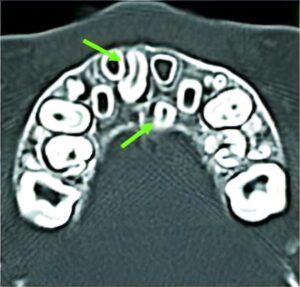

埋伏歯

上顎の左右切歯の間に、余計な歯(過剰歯)が埋まっていることがあります。上顎前歯の歯並びに影響する場合、抜歯が必要になることもあります。